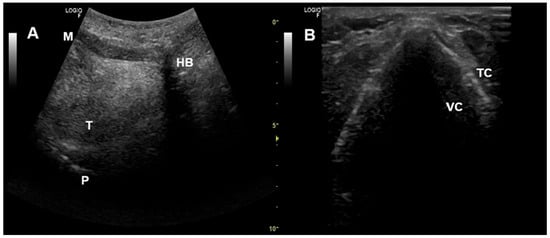

- Sarasate, M.; Córdoba-Izquierdo, A.; Farrero, E.; López-Lisbona, R.; Díez-Ferrer, M.; Trias-Sabrià, P.; Plana, M.; Povedano, M.; Santos, S.; Prats, E. Effect of Noninvasive Ventilation on the Upper Airway in Patients with Amyotrophic Lateral Sclerosis: The Role of Upper-Airway Endoscopy. Respir. Care 2025, 70, 1075–1083. [Google Scholar] [CrossRef]

- Sayas Catalán, J.; Jiménez Huerta, I.; Benavides Mañas, P.; Luján, M.; López-Padilla, D.; Arias Arias, E.; Hernández Voth, A.; Rabec, C. Videolaryngoscopy with Noninvasive Ventilation in Subjects with Upper-Airway Obstruction. Respir. Care 2017, 62, 222–230. [Google Scholar] [CrossRef] [PubMed]